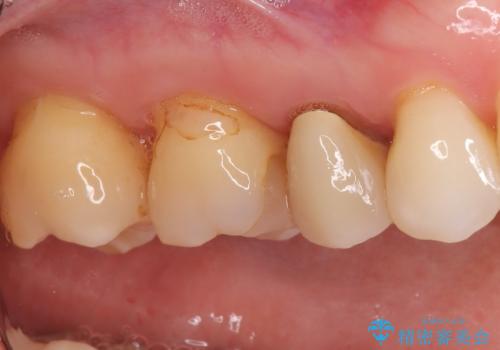

- 右上の奥歯(5番・6番)の被せ物の適合が悪く、歯ぐきが腫れやすい状態でした。患者さんご自身も「物がつまりやすい」「違和感がある」との訴えがあり、レントゲンと視診を行ったところ、被せ物の下にむし歯が進行していることが判明しました。特に右上5番は、神経の治療(根管治療)が過去に行われていましたが、根の先に炎症が残っており、治療のやり直しが必要と判断しました。

まずは両歯の古い被せ物を慎重に除去し、中のむし歯を確認しました。右上5番は神経の治療のやり直し(再根管治療)を行い、細菌感染を取り除いたうえで、根の中を密に封鎖しました。治療中は仮歯を入れて審美性と機能性を保ちつつ、歯ぐきの状態も改善していきました。